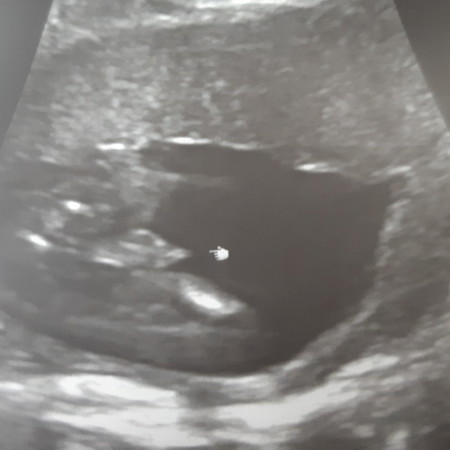

อัลตราซาวน์ 17 w 2 d

แม่ๆเห็นอะไรในภาพคะ โปรดอภิปราย

เห็นจู๋น้องค่ะแม่😁😁

ดูไม่ออก อิอิ